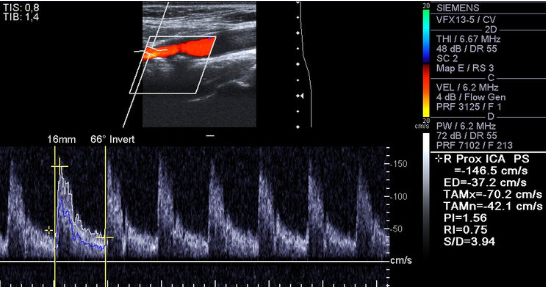

Consider this image.

1. Which vessel is is sample gate positioned?

2. Is the cursor parallel to vessel wall?

3. Is velocity measurement reliable? Why or why not?

4. How would you optimize image? List two items

Rt ICA prox

No

No because the angle is off and its over 60 which will make the velocities higher than they actually are

Decrease depth, move color box up, move sample gate up, fix pw angle, adjust pw ain